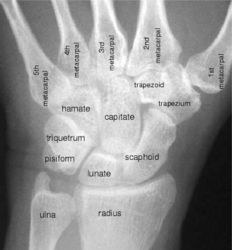

The wrist is a diarthrodial anatomical joint consisting of 8 small bones (scaphoid, capitate, hamate, lunate, trapezium, trapezoid, triquetrum, pisiform) and 7 long bones (radius, ulna, and 5 metacarpals). When subject to injury and disease the wrist undergoes changes in kinematics, inter-bone joint space areas, cartilage thickness, length of ligament paths, etc. Developing computational tools for the analysis of anatomical joint characteristics is important in understanding the cause of injury, tracing the progress of disease, and taking preventative measures.

X-ray of the wrist with bone names